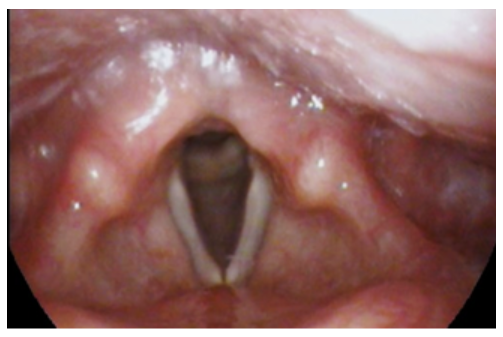

Example of vocal cord atrophy/aging voice.Vocal fold atrophy, also often called "aging voice" or "presbyphonia," is a voice condition characterized by thinning of the vocal fold muscles and tissues. This loss of muscle bulk often results in a curved appearance that prevents the vocal folds from closing normally when speaking or singing. Other surrounding laryngeal muscles may squeeze more tightly to compensate for the reduced vocal fold closure.

• Video Laryngostroboscopy: Using a small camera inserted through the nose or mouth, our specialists are able to assess the health and function of your larynx (voice box) and assess for structural or functional changes associated with aging (curvature along the length of the vocal folds and incomplete closure of the vocal folds during voicing tasks). Click the link to learn more.